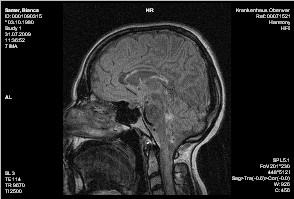

HWS:

Am besten auf der STIR-Sequenz sichtbar finden sich weiträumige T2w Hyperintensitäten im gesamten Myelon, beginnend auf Höhe von C1. Ein Kontrastmittelenhancement ist hierbei nicht erkennbar. Im übrigen geringradige degenerative Wirbelsäulenveränderungen, dargestellt als dorsale Discusvorwölbungen. Hierbei im Segment C3/4 mediolateral bds. am ausgeprägtesten. Insgesamt kein hochgradiger Discusprolaps sowie keine signifikante Wurzelbedrängung.